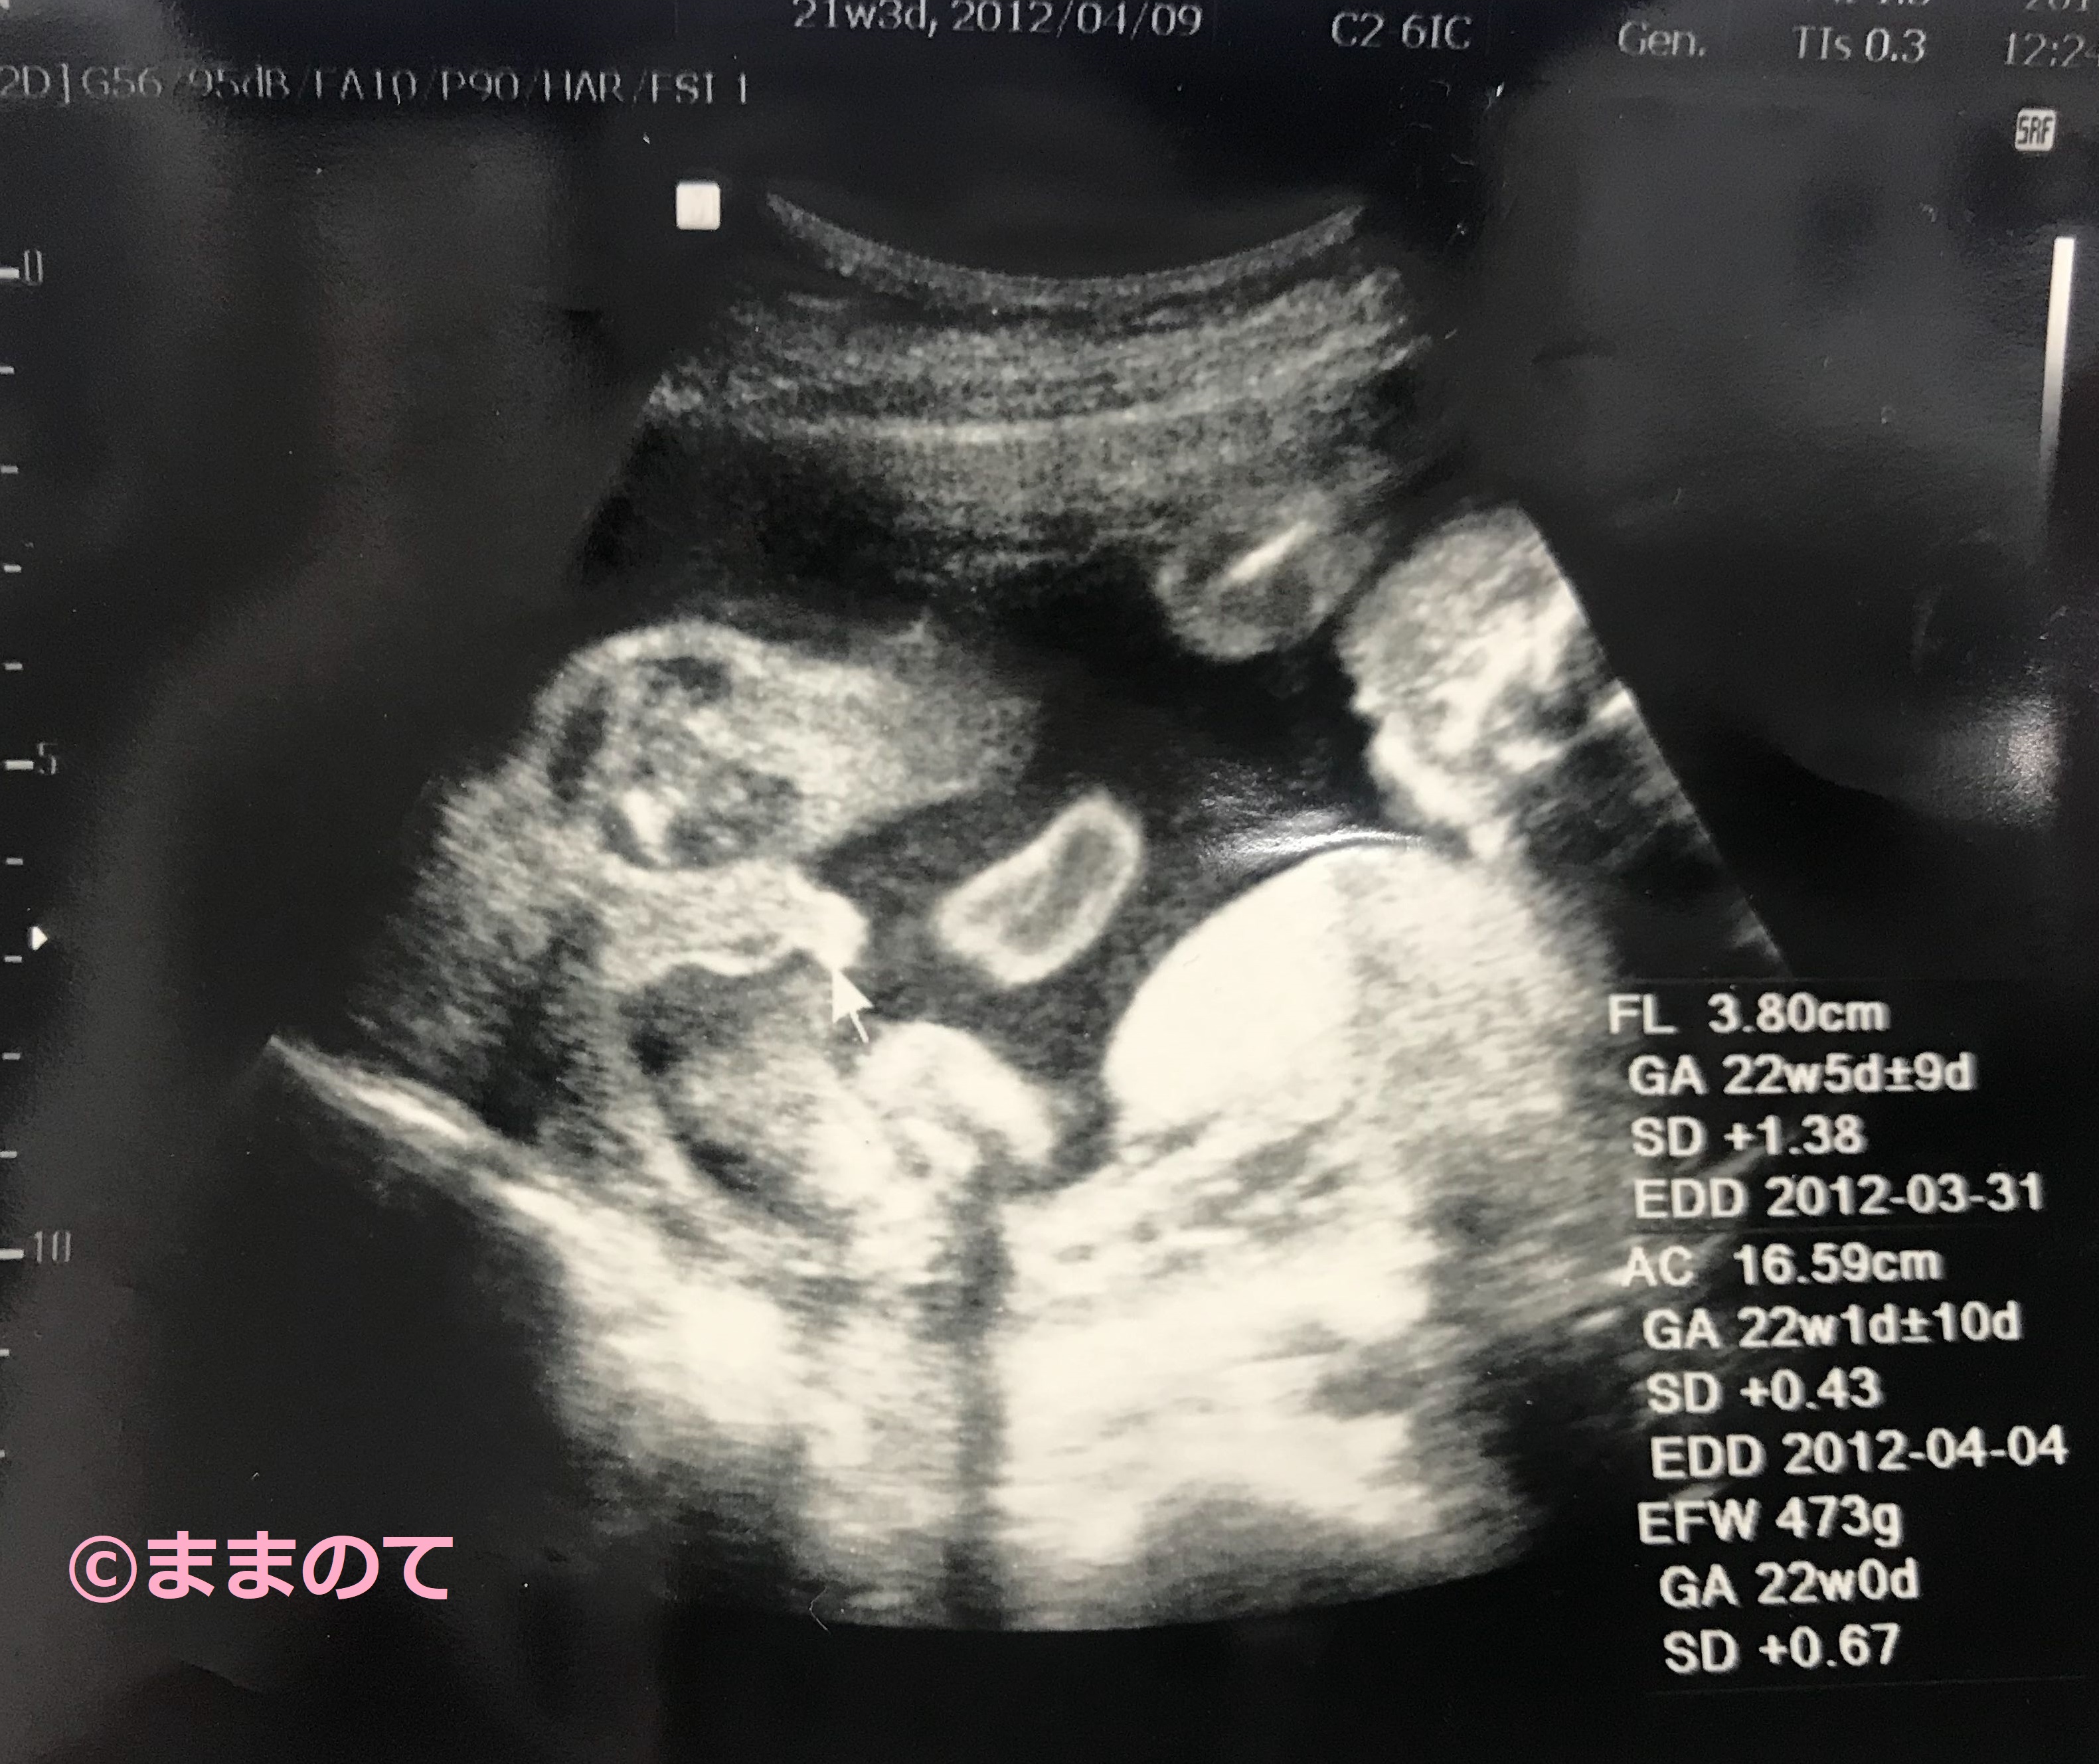

妊娠21週のエコー写真